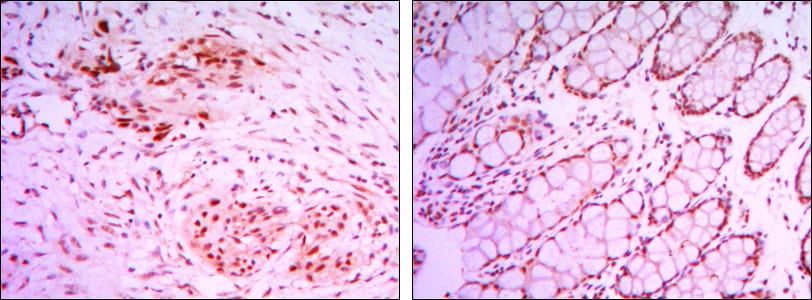

分类: 科研抗体货号: 30077别名: Bcl-2; BCL2应用: IHC,IF,FCM反应种属: Human,Mouse